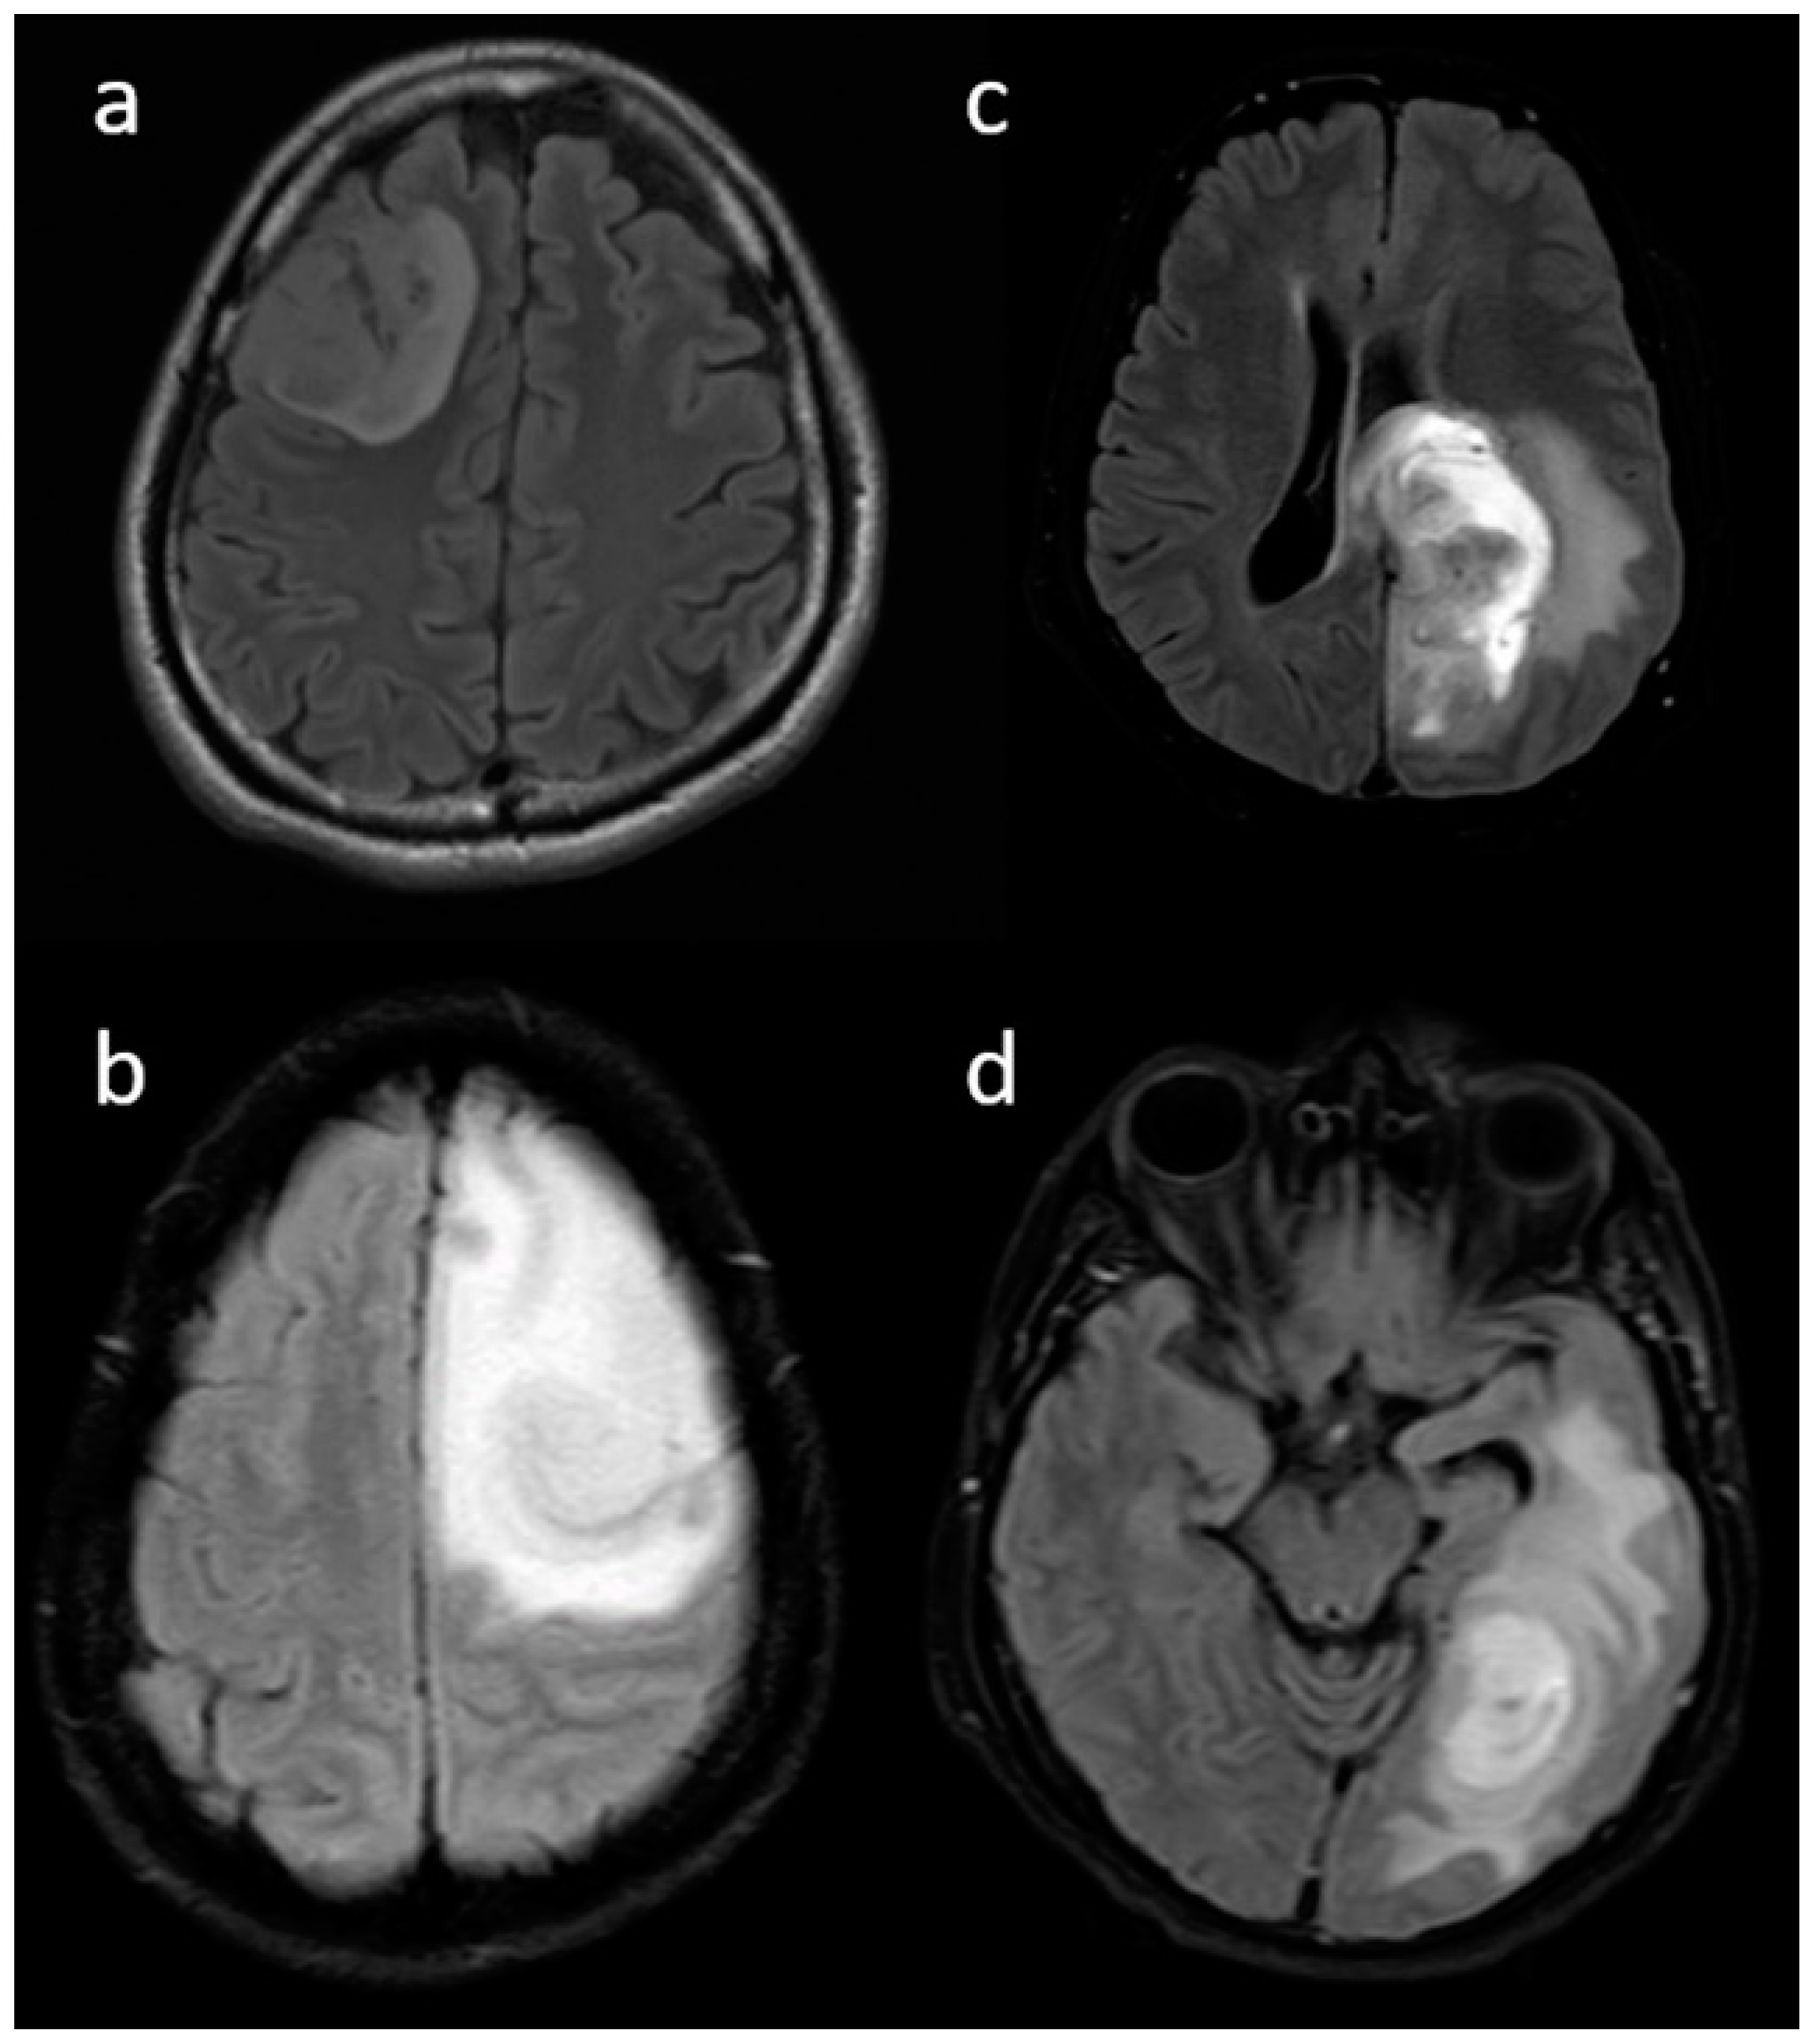

| Enhancement III | Rim | 6 (31.6) | 104 (80.6) | <0.001 |

| Necrosis | None | 3 (15.8) | 3 (2.3) | <0.001 |

| <25% | 11 (57.9) | 14 (10.9) | ||

| 25- 50% | 2 (10.5) | 35 (27.1) | ||

| >50% | 3 (15.8) | 77 (59.7) | ||